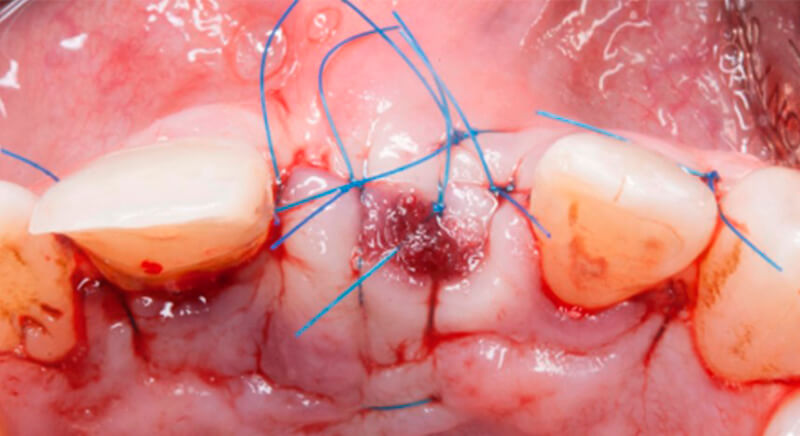

After 6 months of healing, a minimum crestal incision was made to change the 3mm abutment underneath for a 5mm abutment that would be exposed to the oral medium.